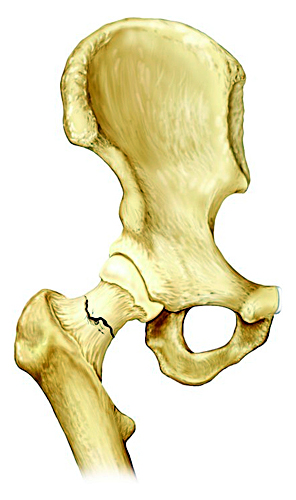

股骨颈(大胯)骨折,如果没有完全断开,或者断开的骨头茬(cha)子之间像两个齿轮的齿一样互相嵌插咬合在一起(我们称之为嵌插骨折),如下图。这时骨折断端之间还是有一定稳定性的。

白箭头所指处,即为股骨颈骨折部位,但因为嵌插而不明显

这个时候,患者虽然骨折了有点疼,但是却可以继续负重行走。很容易让患者误以为没有骨折,觉得只是软组织挫伤。